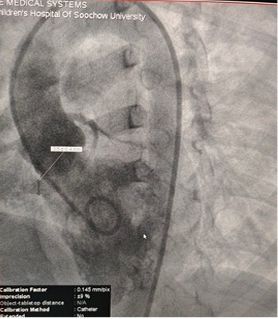

Case Sharing | Successful Closure of Multi-Exit Membranous Septal Aneurysm-Type VSD Using MemoSorb Biodegradable Occluder

Résultats préopératoires de l'écho:

Diamètre de la base: ~ 6,1mm avec plusieurs points de sortie

Tissu semblable à une membrane observé sur le défaut

Doppler couleur: flux de shunt de gauche à droite

Diagnostic: VSD Périmembraneux

Selected MemoSorb ABFDQ-II 9 occluder based on intraoperative angiography and echocardiographic assessment.